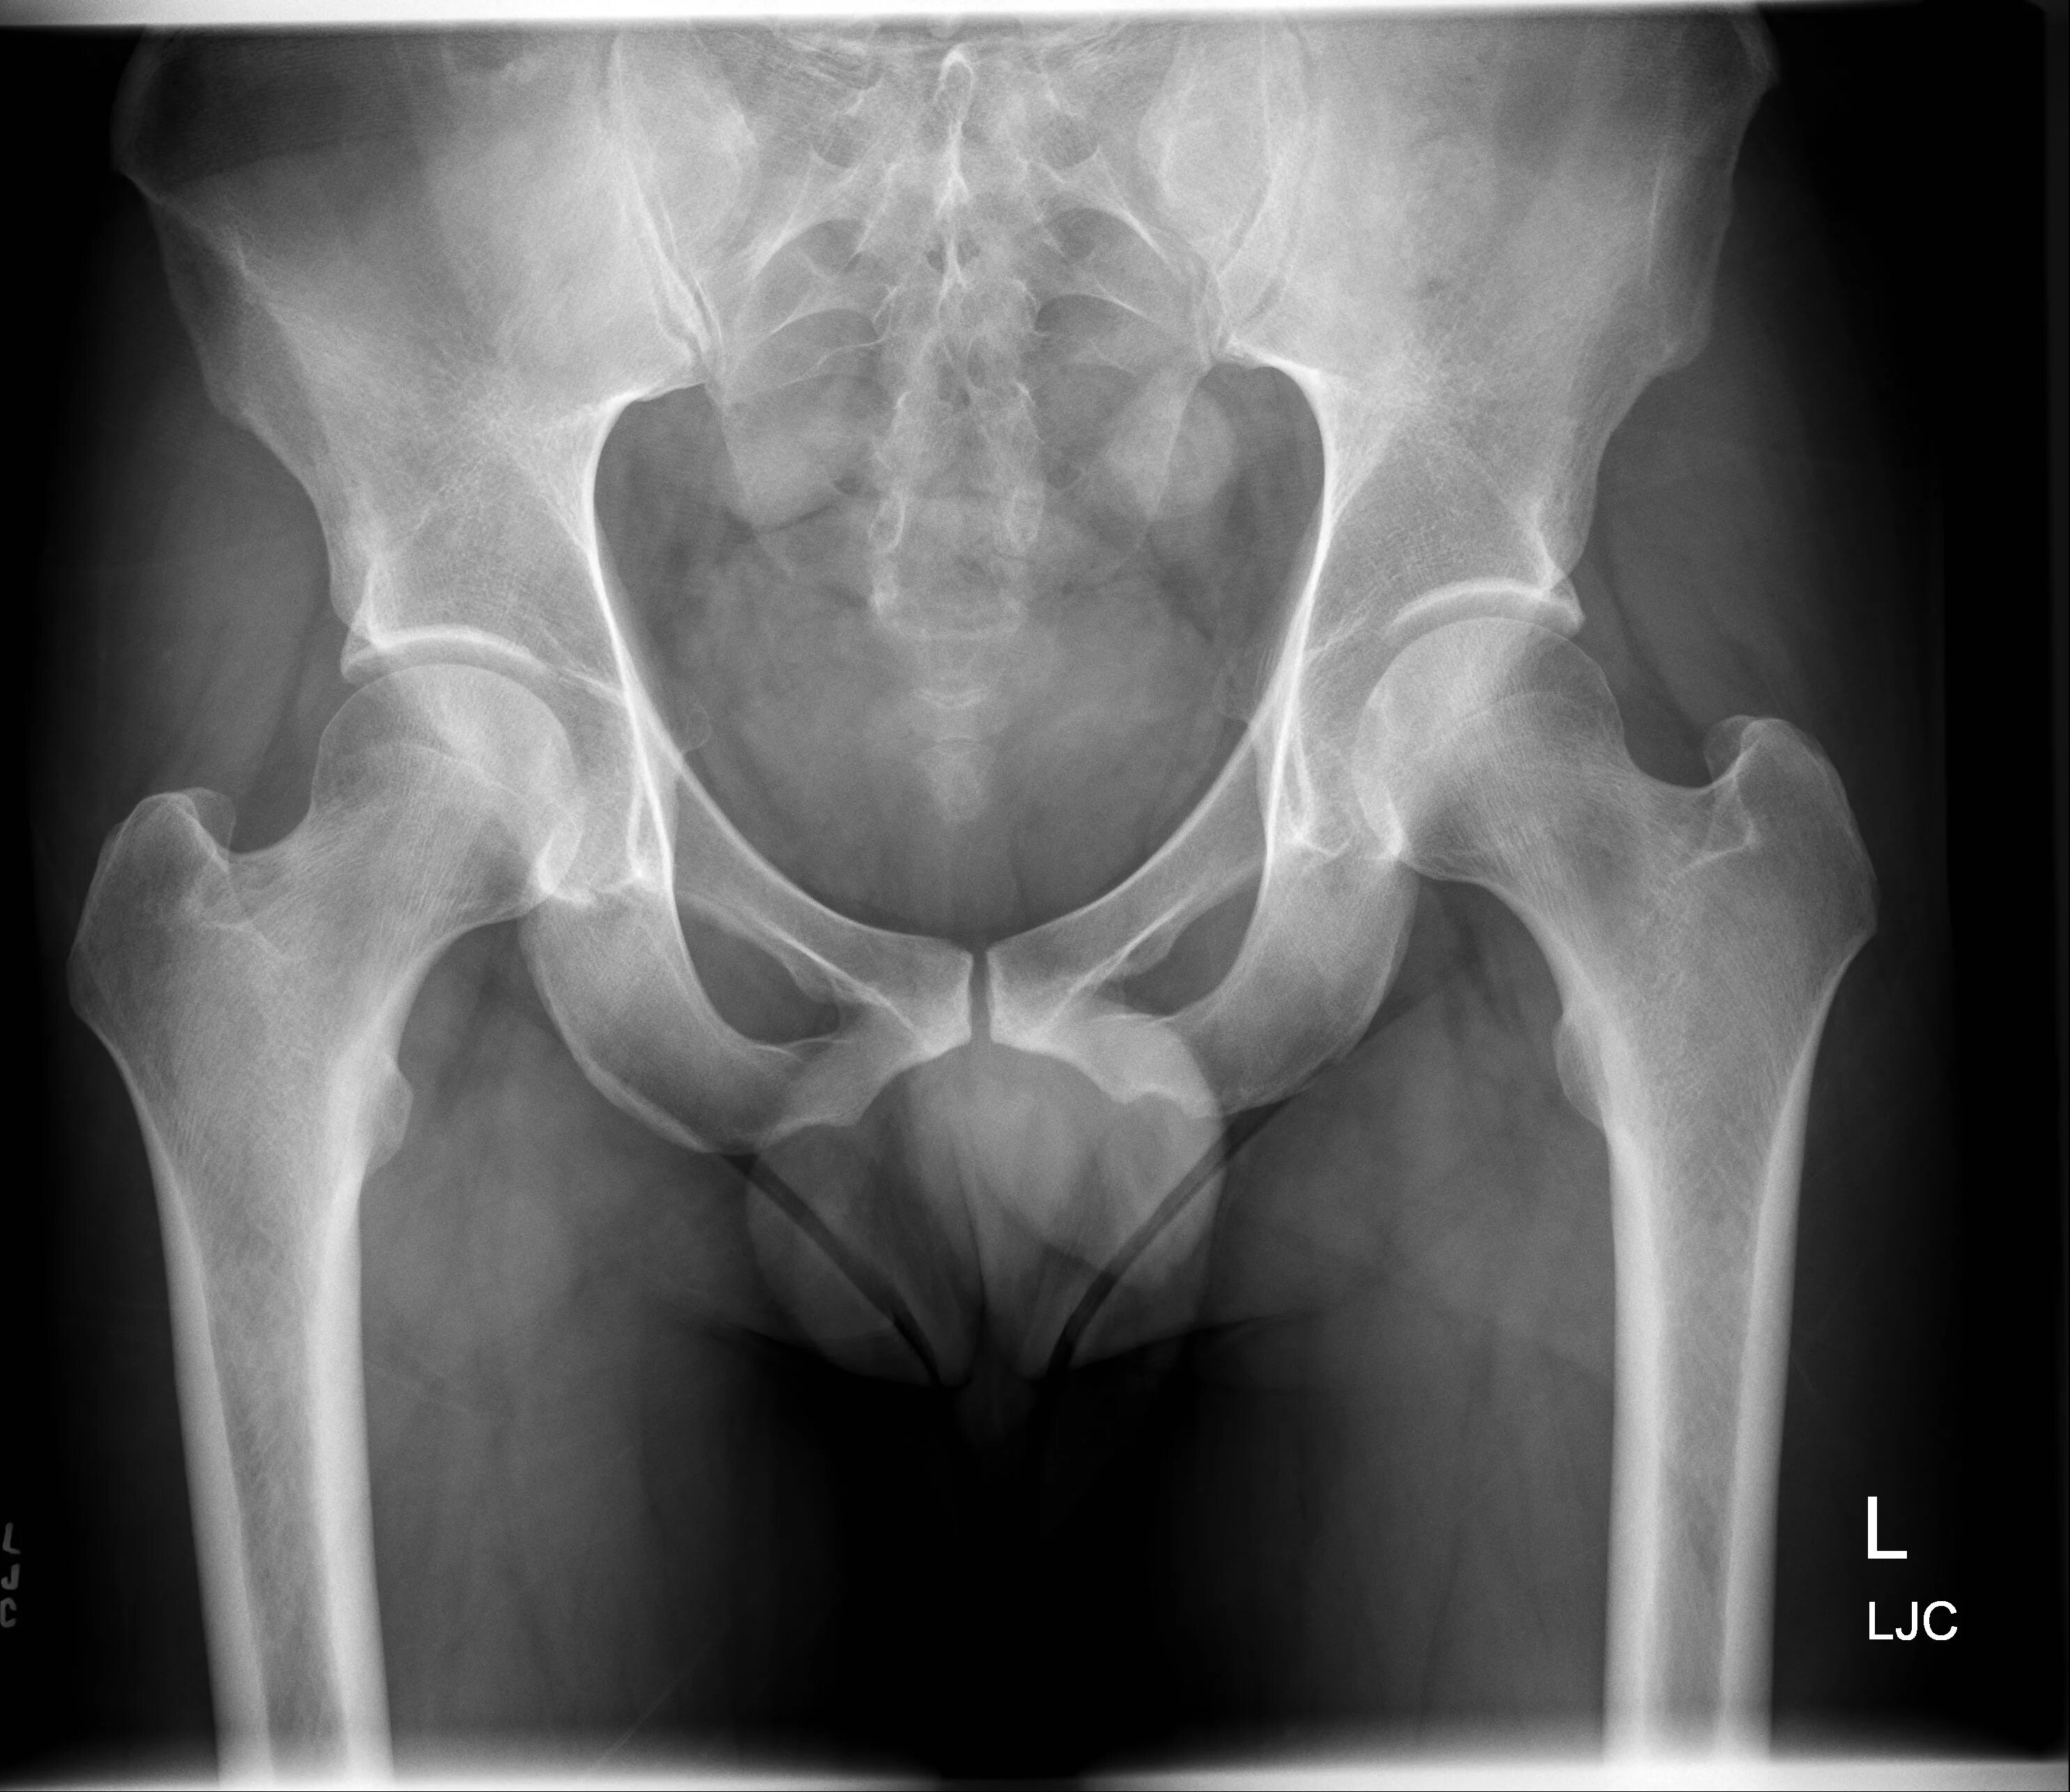

Где x ray